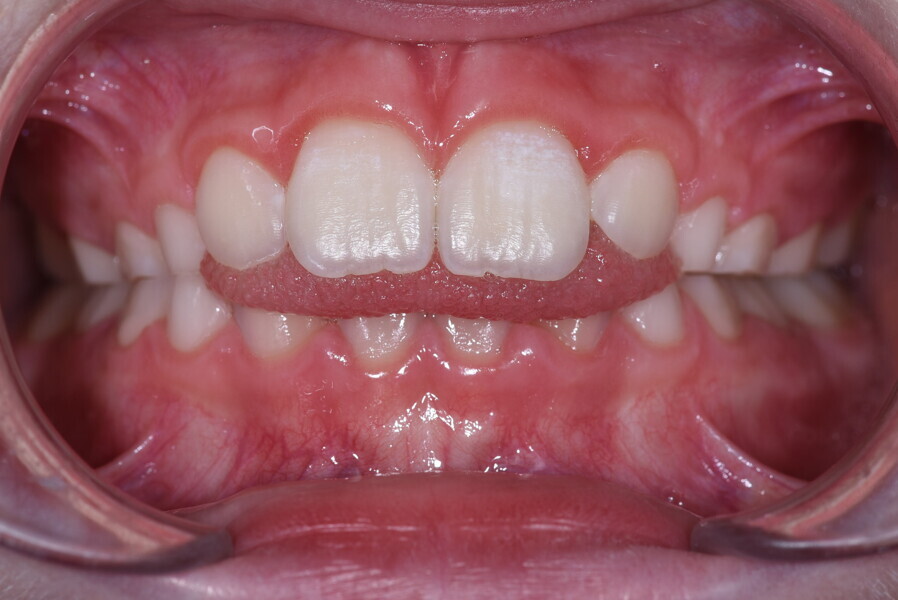

After the first phase of aligner treatment, we had achieved better inter-arch coherence, better maxillary arch expansion, and some space for improving the anterior tooth proportions restoratively (Fig. 19). We then temporarily restored the anterior teeth directly with composite, closing the spaces, improving the tooth proportions and further increasing the maxillary arch expansion (Fig. 20). We used restorative arch expansion to reduce the orthodontic destabilisation of the teeth to achieve the correct inter-arch coherence and retain the teeth in the cortical bone.38 A refinement aligner phase was undertaken to improve the final alignment of the gingival zenith and to improve the inter-arch coherence (Fig. 21). The periods of the first orthodontic phase and of the refinement were used to augment the mandibular and maxillary bone and to place the implants (Fig. 22). At the end of the orthodontic treatment, the case was finalised with ceramic veneers in the anterior area and temporary restorations on the implants in the posterior area (Figs. 23–26).

The provisional phase of about four months was important to allow the peri-implant tissue to mature and to teach the patient to chew correctly with chewing gum, cotton rolls and silicone masticatory sticks. This is fundamental training for the patient to achieve the correct alternating unilateral masticatory cycle needed to obtain the ideal rehabilitation of the masticatory system. We wanted the patient to achieve ideal masticatory and swallowing function. After sufficient rehabilitation time, we finalised the case with posterior zirconia crowns screwed on to the implants (Fig. 27).26

Our ideal final rehabilitation goals were:

• posterior stability;

• inter-arch coherence and U-shaped arches;

• anterior freedom during mastication;

• minimum disclusion vertical dimension;

• alternating unilateral masticatory cycle;

• physiological swallowing and high tongue posture against the palate; and

• mandibular disclusion advancing the mandible freely.

For maintenance purposes, after prosthetic finalisation, the patient was to carry on with the Froggymouth therapy and to use the Ri.P.A.Ra. for physiotherapeutic exercises and mastication training (Fig. 28). It was strongly recommended that the patient wear a mandibular occlusal splint during sleep. This occlusal splint was designed with disclusion guides to advance the mandible and ensure balanced contralateral support (Fig. 29).11, 39 We achieved an aesthetic appearance with adequate inter-arch coherence and a better cephalometric result (Figs. 30 & 31).